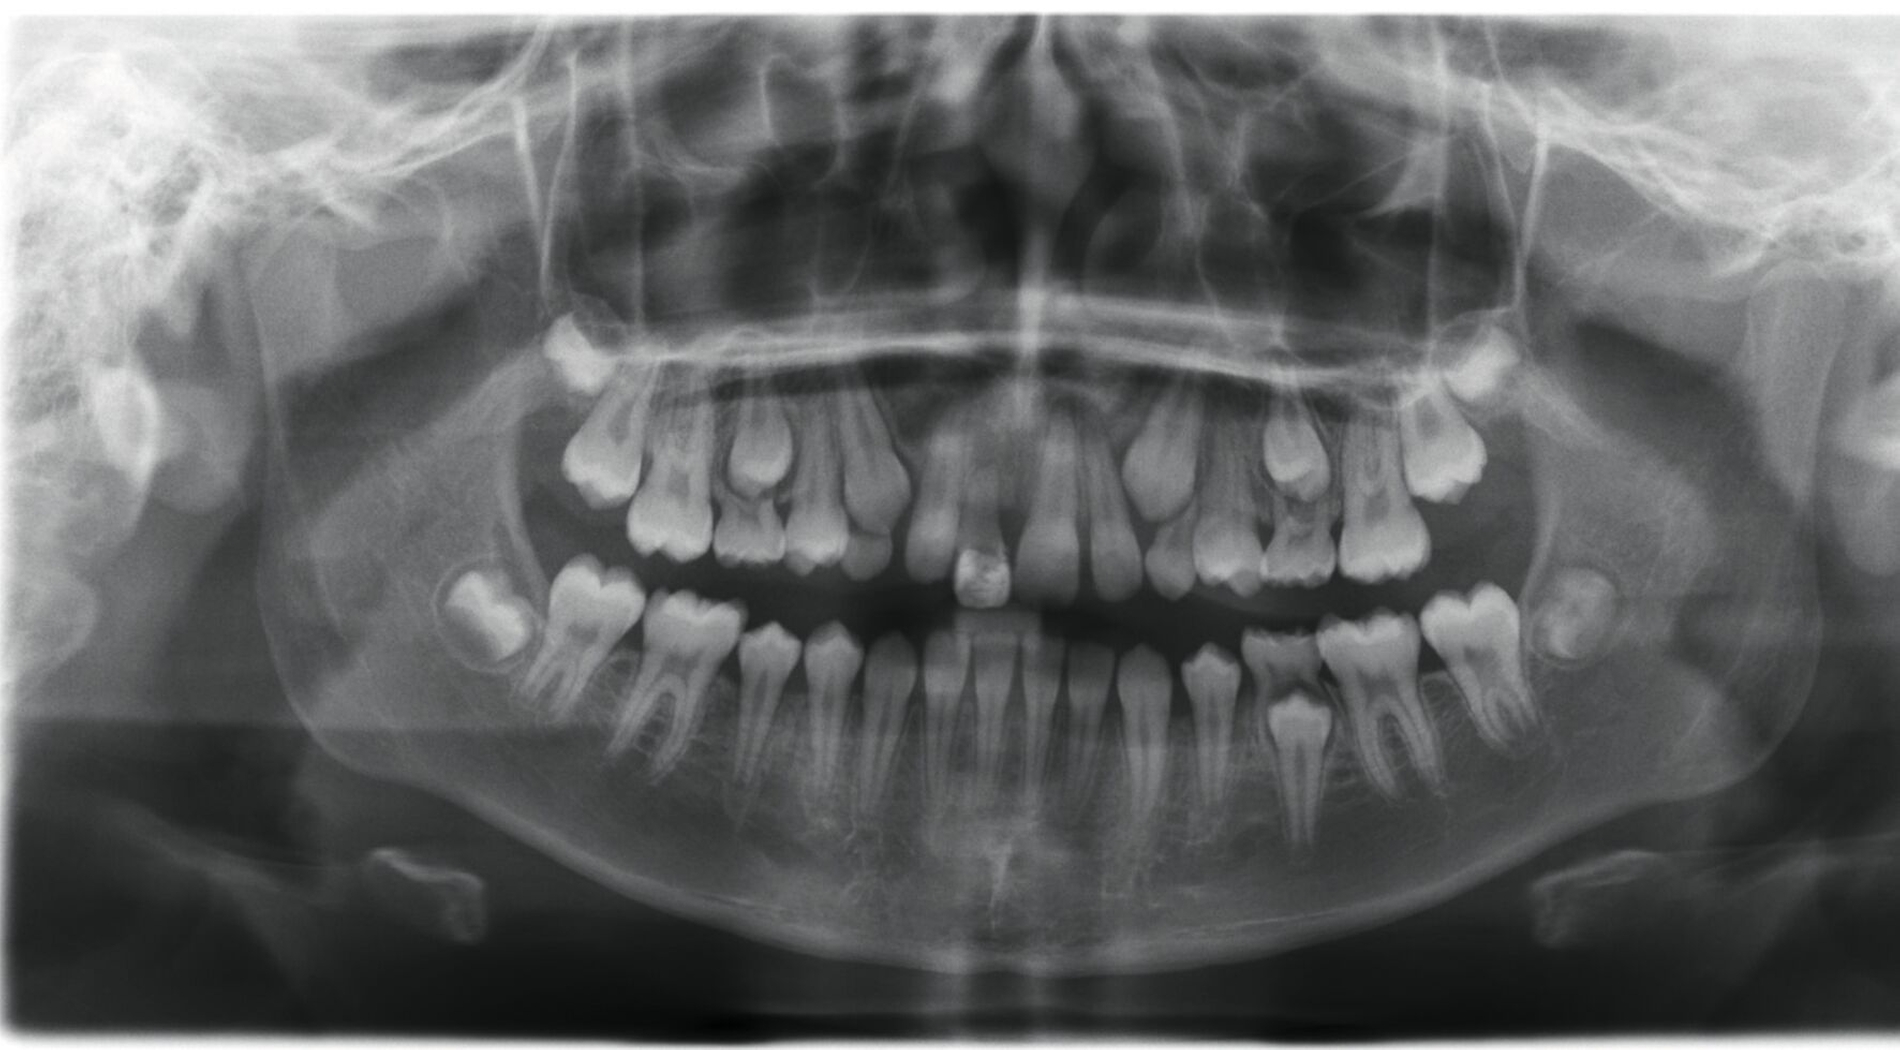

Ein neunjähriges Mädchen hatte bei einem Schlittenunfall den rechten oberen mittleren Schneidezahn verloren. Der Zahn 11 war nach einer extraoralen Lagerungszeit von mehr als 24 Stunden alio loco replantiert und mit einem Titan-Trauma-Splint von Zahn 12 bis 22 geschient worden. Drei Monate nach dem Unfall stellte sich die Patientin mit folgendem Befund vor (Abbildung 2):

Im OPG findet sich nach Replantation mit Pulpotomie (Abbildung 2a) bereits ein vertikaler Einbruch des krestalen Knochens, drei Monate später ist eine infektionsbedingte Resorption des Zahnes 11 erkennbar (Abbildung 2b). Alle vier Milcheckzähne zeigen im Alter von neun Jahren bereits deutlich reduzierte Wurzellängen aufgrund der natürlichen Exfoliation durch die im Durchbruch befindlichen bleibenden Eckzähne. Die Entscheidung fiel auf den Zahn 83 als Autotransplantat, da dieser zu diesem Zeitpunkt die längste Wurzel aufwies (Abbildung 2b).